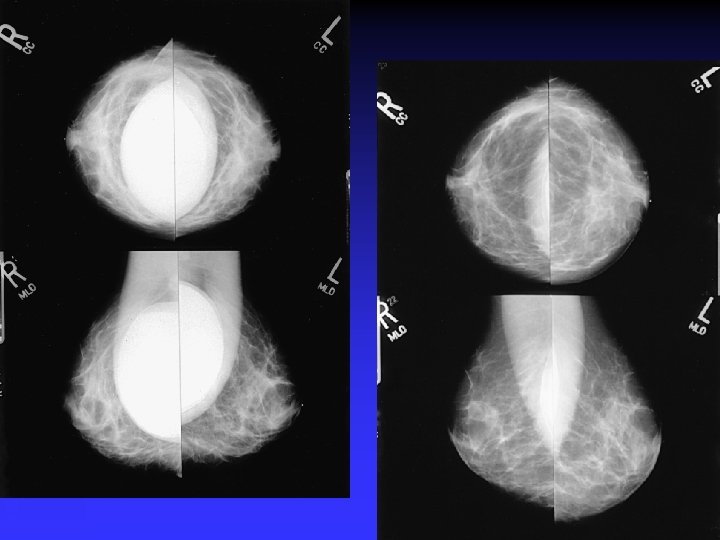

THE AUGMENTED BREAST Difficulty with IMPLANTS

importance of high-quality mammograms is evident in the two images of the same breast